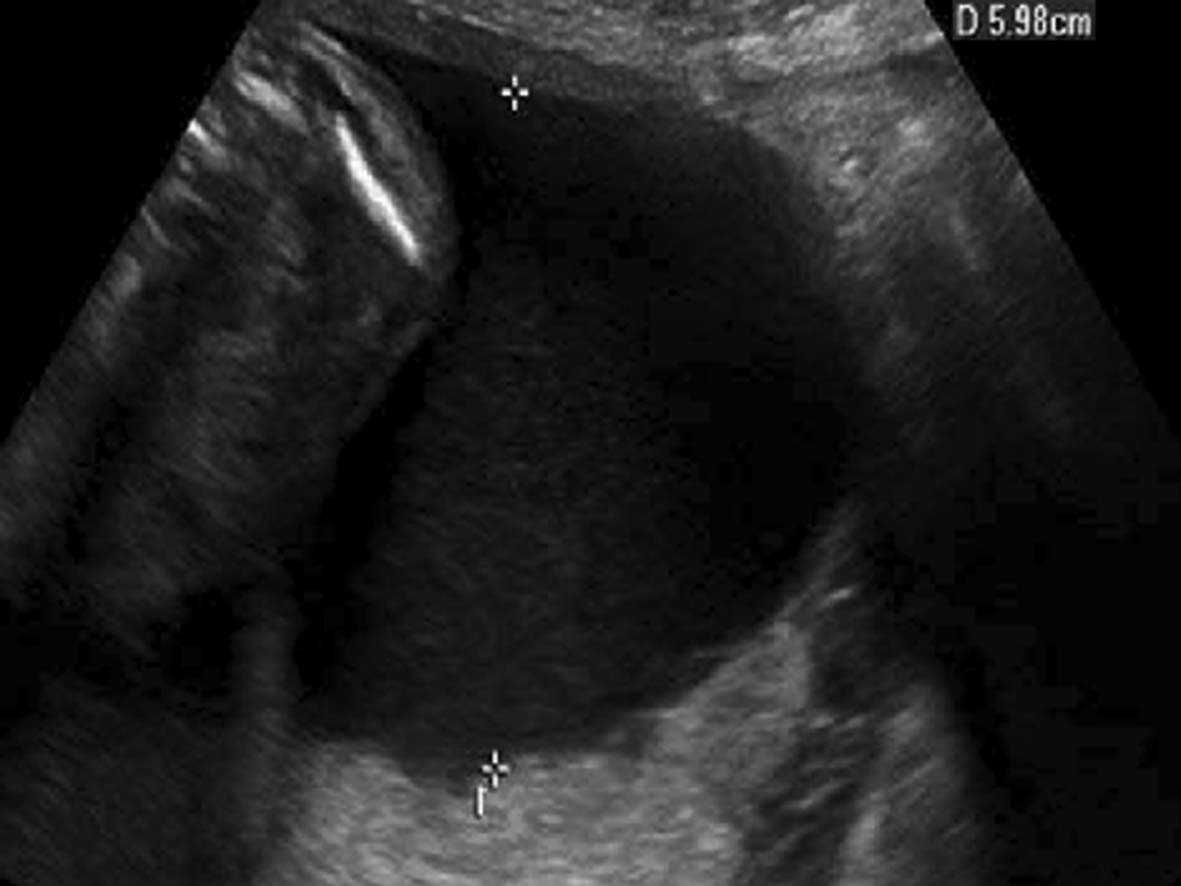

2.羊水池内径测量法 将探头垂直于子宫壁,测量羊膜腔内侧壁至胎体最大的距离,此即羊水池的最大内径。以获得的数值衡量羊水量多少。正常时羊水池内径4~6cm。小于2cm为羊水过少,大于8cm为羊水过多。也有研究者将超声探头垂直于水平面,测量羊水池最大的垂直深度。这种方法也被称为羊水池最大垂直深度测量法(图3)。

图3羊水池最大内径测量

早期有笔者以羊水池最大垂直深度小于1cm时为羊水过少的标准,亦称为1cm原则。但Bottom等注意到羊水池最大深度不足1cm是非常罕见的,认为用此指标预测不良妊娠结局的敏感性很差。

超声显像检查使用羊水池内径测量法评价羊水过多或过少时需要注意显示脐带的回声,避免选择脐带聚集区作为羊水池最大深度进行测量,而出现此征象恰恰提示羊水过少。多切面、多区域的检查辨认、综合评价羊水过多或过少是重要的。单纯以测量数字来判断羊水过多或过少有时是不准确的,应当全面观察分析,结合胎儿在宫腔内的位置等情况综合分析,对羊水量做出恰当的评估。